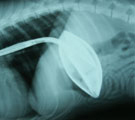

内視鏡 1-g 胃内異物-軟式用テニスボール

柴犬、オス、2歳5ヶ月。体重8.96kg。「軟式用テニスボールを飲み込んだが吐き出さない。内視鏡で取ってほしい」とのことで来院。

経過:一般状態良好。一部裂けて穴があいているテニスボールを飲んだという。上腹部X線で胃のほぼ全内腔を占める異物が認められた。椀状につぶれたテニスボールと考えられた。24時間絶食後、全身麻酔下、胃内視鏡検査を施行した。最初は、外径6mmの内視鏡に外付チャネルを設置し、大型の鰐口把持鉗子にてちょうどボールの裂け目を把持して慎重に胃内より牽引し何とか噴門を通過させた。しかし、胸部食道内で大きな抵抗が生じ鉗子が抜けて滞留してしまった。次に、透視および内視鏡観察下に食道内に内視鏡用マニセプスを挿入しそれでしっかり異物を把持し、慎重に牽引して異物回収に成功した。直径6cmの軟式用テニスボールであった。表面は腸液と胃液で変色していた。かなり悪戦苦闘し処置時間は71分だった。経過良好で当日退院した。